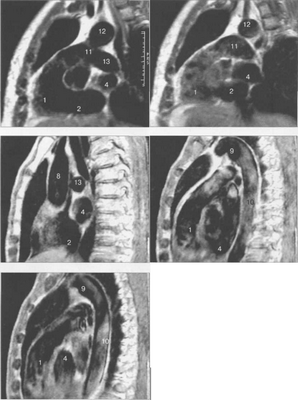

Рис. 9.48. MPT сердца. Сагиттальная плоскость.

Рис. 9.49. МРТ сердца. Двухкамерные сечения.

Рис. 9.50. МРТ сердца. Фронтальные сечения.

Рис. 9.51. МРТ сердца. Сечения по короткой оси левого желудочка.

Рис. 9.52. МРТ сердца. Четырехкамерные сечения.

На рис. 9.47—9.52 представлены Т1-ВИ наиболее часто используемых МР-сечений сердца.

Здесь и на рис. 9.48—9.52:

I — правый желудочек, 2 — левый желудочек, 3 — правое предсердие, 4 — левое предсердие, 5 — межжелудочковая перегородка, 6 — межпредсердная перегородка, 7 — задняя стенка левого желудочка, 8 — восходящая часть аорты, 9 — дуга аорты, 10 — нисходящая часть аорты, 11 — легочный ствол, 12 — правая легочная артерия. 13 — левая легочная артерия, 14 — верхняя полая вена, 15 — нижняя полая вена, 16 — трахея.